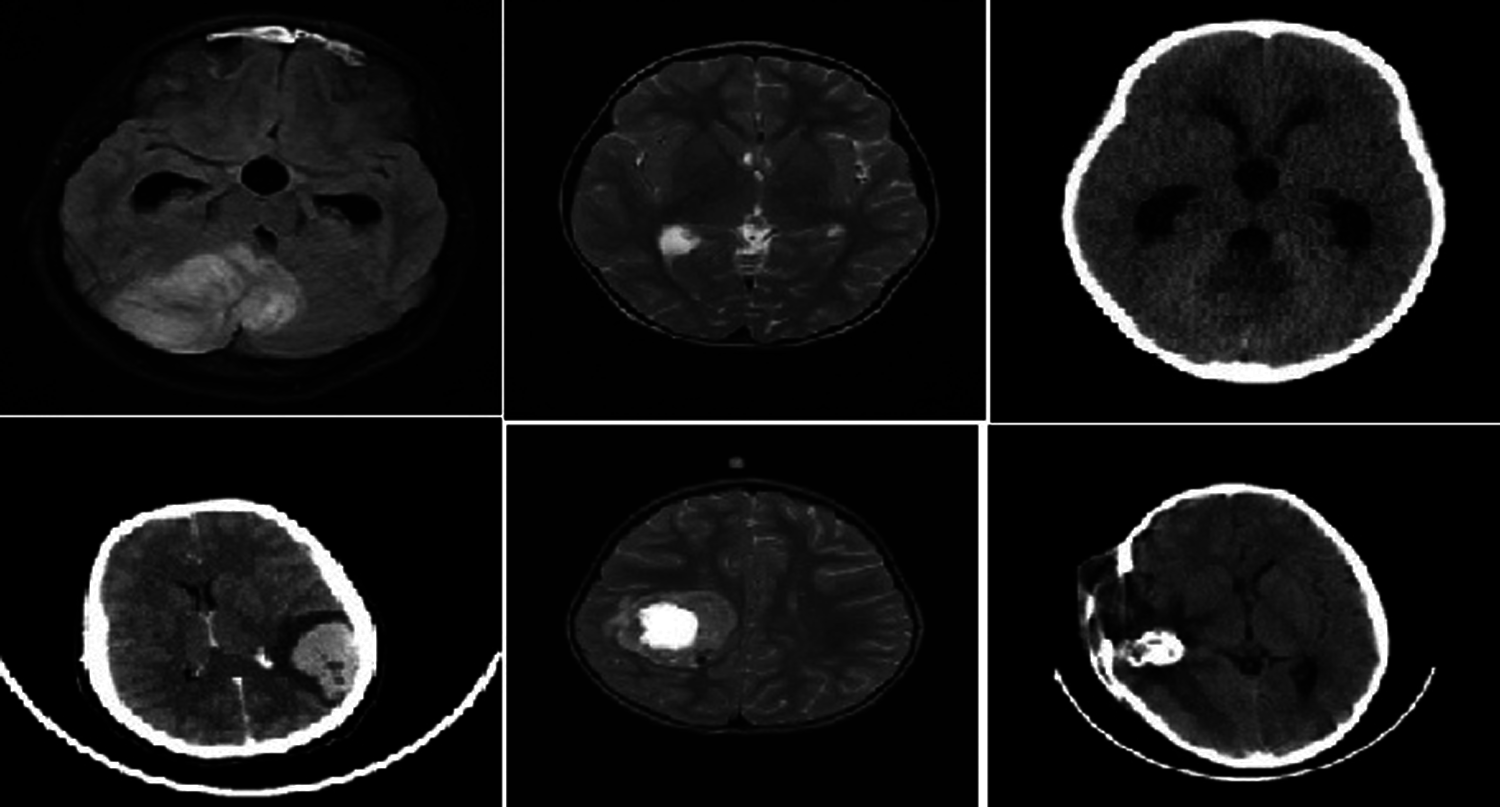

NBIA comprises a searchable repository of vivo images that ensure the biomedical research persons, industrial experts and academic profession to extract image archives to be utilized in the area of development and validation of medical image classification. This is highly suitable for detecting lesion, classifying the images, diagnosis, quantitative assessment, providing feedback and so on. The parameter settings have the intensity values in the range of 0.2 to 1 which is tabulated in Tab. 1. The sample brain images also are given below in Fig. 4.

Figure 4: Sample brain tumor images